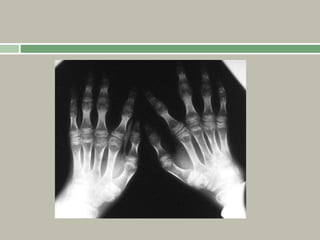

Relative shortening of the middle finger gives the

appearance that all fingers are the same length

(‘starfish

hand’). An abnormally increased separation of the

middle and ring fingers gives the hand a ‘trident’

appearance.

The tubular bones (including those of the hand and

feet) appear short, but with a relative increase in

their density and diameter.